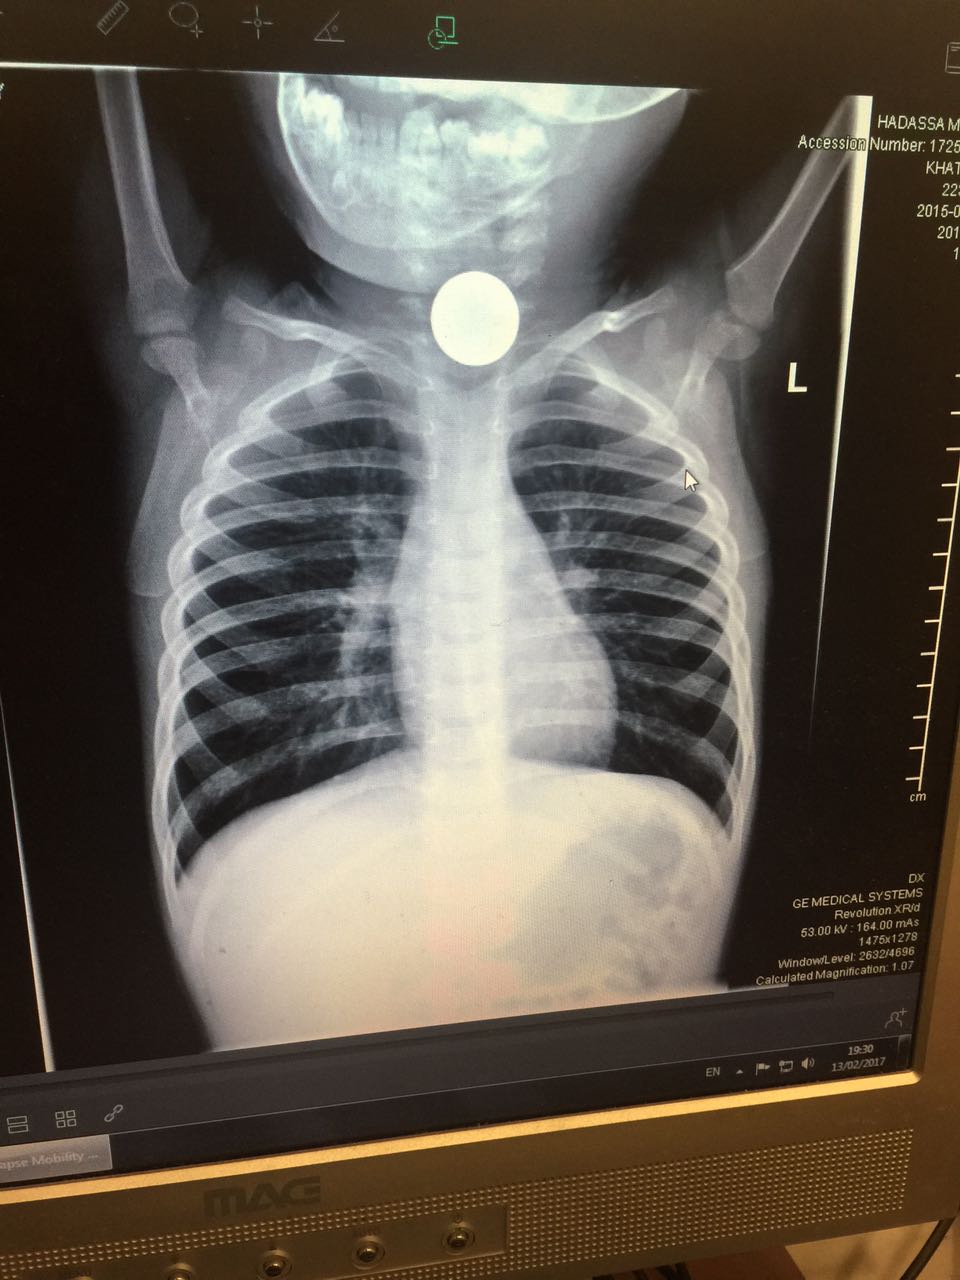

סדרת בדיקות ובכללן בדיקת רנטגן הבהירו ללא כל צל של ספק כי חפץ עגול ושטוח היה נעוץ בוושט של הפעוט. ד"ר מרדכי סליי, רופא גסטרו ילדים בכיר הוזעק בדחיפות למיון ילדים והחל בפעולות חילוץ מידיות של החפץ אשר עלול היה לגרום לסיבוכים ניכרים עד כדי התערבות ניתוחית ואף לסיכון חייו של הילד.

"היה ברור כי הילד במצוקה" אמר ד"ר סליי. "על מנת לבצע את הפרוצדורה, היה צורך להרדימו. החפץ גלש לקיבה ומשם שלפנו אותו בזהירות רבה. אז התברר כי הפעוט בלע מטבע של עשר אגורות, כאשר אף אחד לא שם לב".